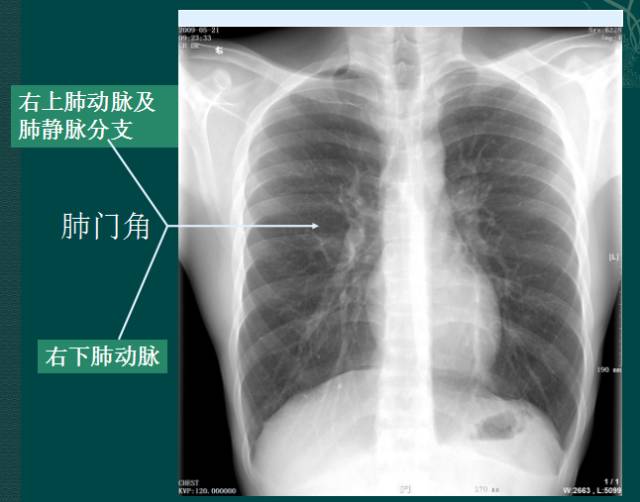

x线肺门指肺动脉、肺叶动脉、肺段动脉、伴行支气管以及肺静脉构成。

右肺门可分为上、下两部。上部约占1/3,由上肺静脉、上肺动脉及下肺动脉后回归支构成。上肺静脉下后干构成右上肺门的外缘;右肺门下部 约占2/3,由右下肺动脉干构成,其正常宽度不超过15mm,沿中间段支气管外缘平行向外下走行。右肺门上、下部相交形成一钝的夹角,称肺门角,正常该角顶清晰。如下图

左肺门亦分为上、下两部。上部由左肺动脉及其分支、左上叶支气管和左上肺静脉及其分支构成;下部由左下肺动脉及其分支构成,常被心影所遮盖。